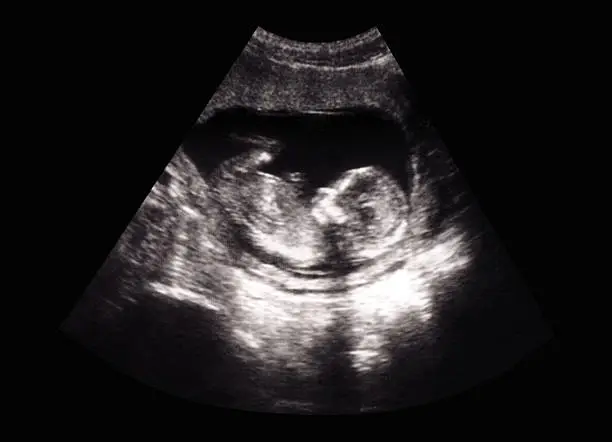

이러한 경우, 초음파 검사나 혈액 검사를 통해 정확한 진단을 받는 것이 필요합니다. 또한 출혈이 지속될 때는 스트레스나 과도한 활동을 피하고, 휴식을 취하는 것이 좋습니다. 이는 몸이 회복하는 데 도움을 줄 수 있으며, 불필요한 추가 출혈을 방지할 수 있습니다. 그러나 출혈이 계속될 경우 의사와의 상담을 통해 적절한 치료 방안을 모색해야 합니다.